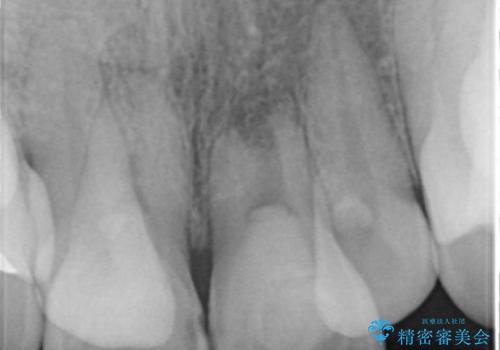

X線写真より、充填剤の突き出た状態の根管治療の再治療を行い、セラミック治療を計画すると同時に、

歯ブラシがしづらく虫歯の原因となっている歯の位置の悪い右上側切歯の抜去を行います。